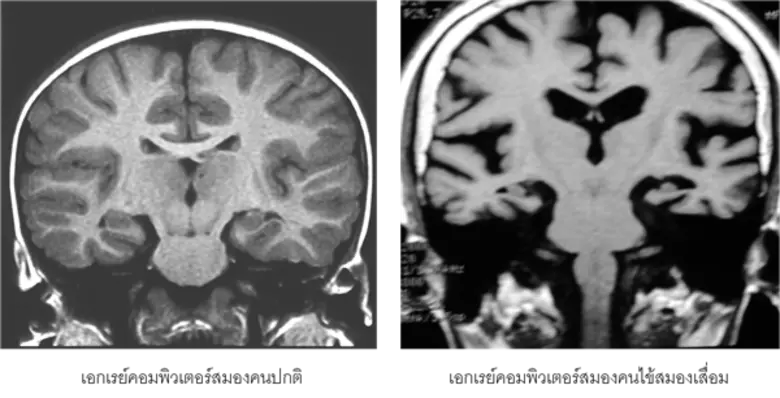

โรคสมองเสื่อมเป็นหนึ่งในกลุ่มอาการผู้สูงอายุ (geriatric syndrome) ที่พบมากขึ้นและกำลังเป็นปัญหาทางสาธารณสุขที่สำคัญของประเทศ สังคม และครอบครัว เนื่องจากเป็นโรคที่พบได้บ่อยในผู้สูงอายุและมีจำนวนผู้ป่วยมากขึ้นตามอายุเฉลี่ยของประชากรที่เพิ่มขึ้น ก่อให้เกิดผลกระทบทางสังคมและเศรษฐกิจของครอบครัวและประเทศชาติ เนื่องจากการดูแลรักษาผู้ป่วยกลุ่มนี้สร้างความลำบากแก่ญาติและผู้ดูแลทั้งทางร่างกายและจิตใจ ทั้งนี้สาเหตุและกลไกที่แท้จริงของการเกิดโรคอัลไซเมอร์ (Alzheimer's disease) ซึ่งเป็นสาเหตุส่วนใหญ่ของโรคสมองเสื่อมนี้ยังไม่ทราบแน่ชัด ถึงแม้จะมีผลงานวิจัยเกี่ยวกับเรื่องนี้มากมายก็ตาม อัตราการเกิดโรคนี้ในผู้สูงอายุจะเป็นแบบทวีคูณ โดยพบผู้ป่วยสมองเสื่อมประมาณร้อยละ โรคอัลไซเมอร์-กรมการแพทย์ ในประชากรอายุ 6โรคสมองเสื่อม-69 ปี ร้อยละ 8 ในประชากรอายุ 7โรคสมองเสื่อม-79 ปี และร้อยละ 5โรคสมองเสื่อม หรือครึ่งหนึ่งของประชากรที่อายุ 85 ปีขึ้นไป